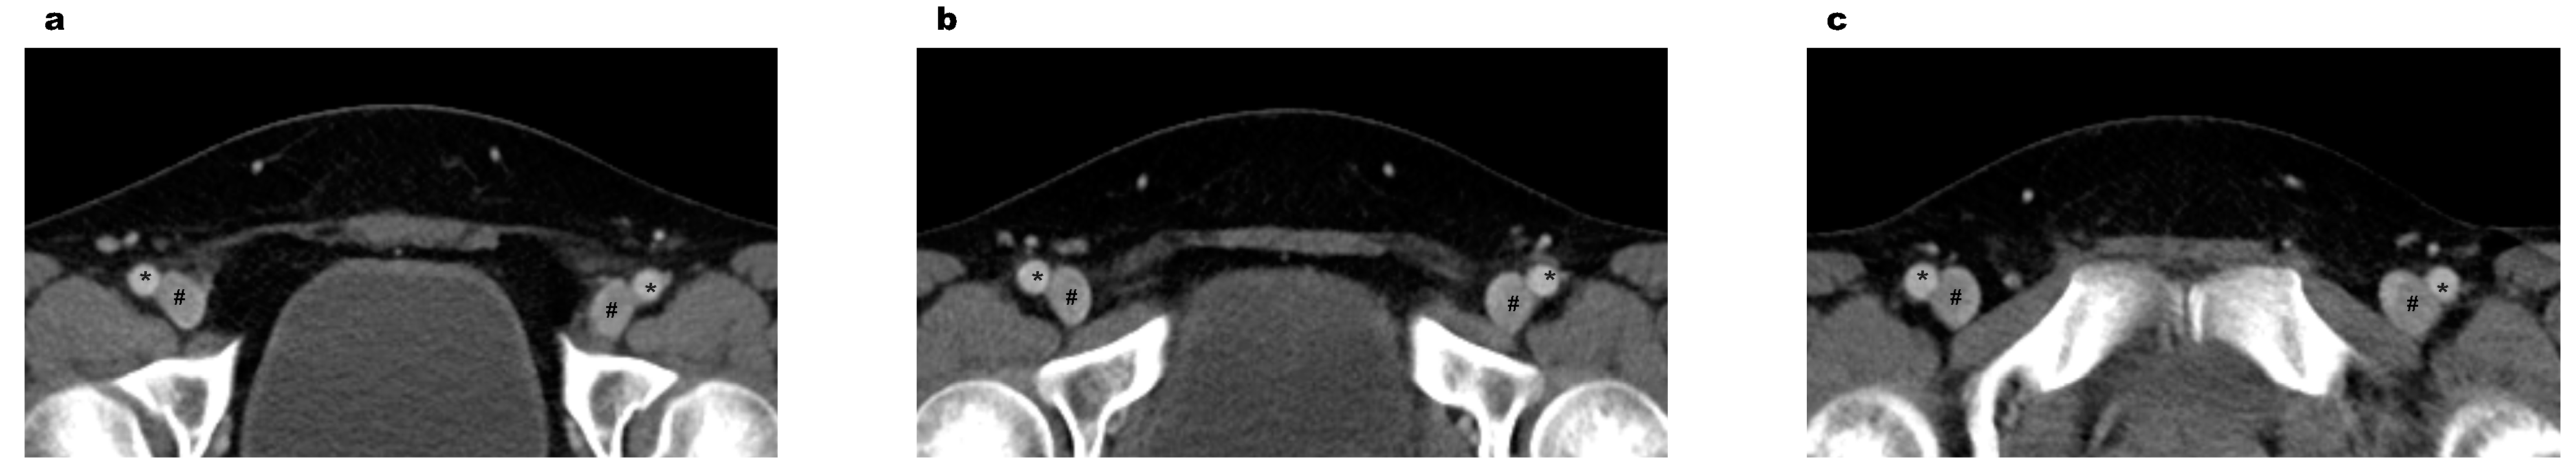

| Morphology types between veins and arteries | ||||

| Proximal | 0.206 | |||

| Type I | 1060 (90.8) | 534 (91.4) | 526 (90.1) | |

| Type II | 102 (8.7) | 48 (8.2) | 54 (9.2) | |

| Type III | 6 (0.5) | 2 (0.3) | 4 (0.7) | |

| Middle | <0.001 | |||

| Type I | 924 (79.1) | 491 (84.1) | 433 (74.1) | |

| Type II | 224 (19.2) | 84 (14.4) | 140 (24.0) | |

| Type III | 20 (1.7) | 9 (1.5) | 11 (1.9) | |

| Distal | 0.011 | |||

| Type I | 680 (58.2) | 359 (61.5) | 321 (55.0) | |

| Type II | 419 (35.9) | 195 (33.4) | 224 (38.4) | |

| Type III | 69 (5.9) | 30 (5.1) | 39 (6.7) | |

| p value | <0.001 | <0.001 | <0.001 | |